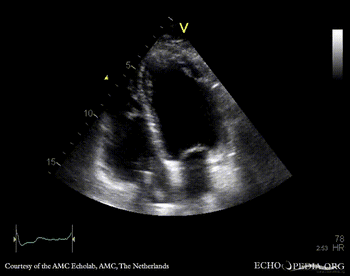

Endocarditis of pacemaker lead

PSAX: mobile structure on pacemaker lead A4CH: mobile structure on pacemaker lead